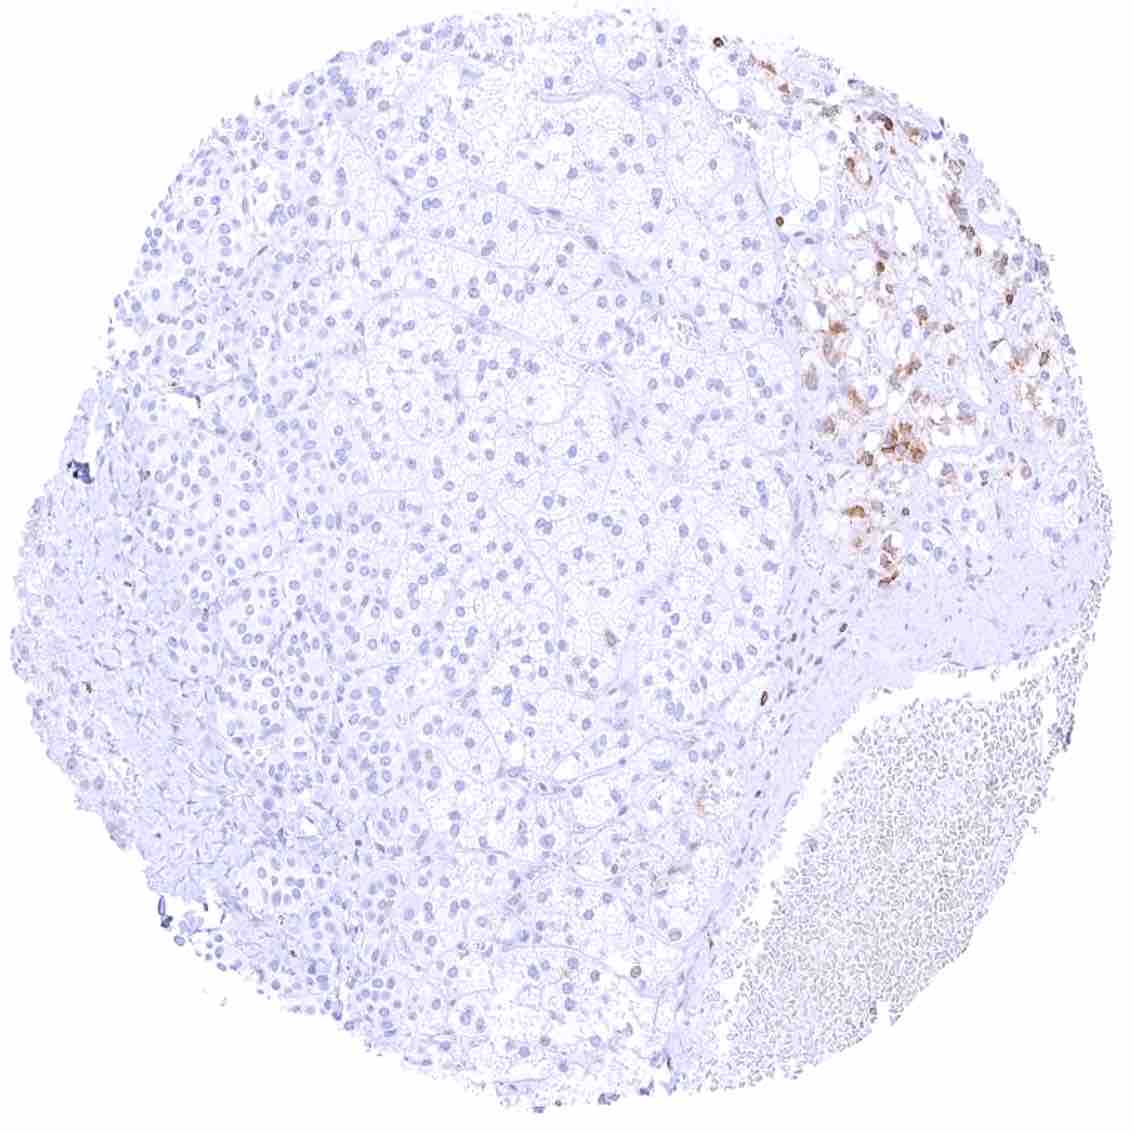

Spleen – Strong bcl-2 positivity of the lymphocytes of the white pulpa and of a small fraction of cells in the red pulpa. .jpeg